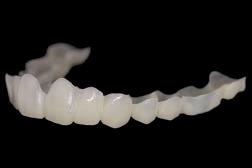

Prettau 3 Dispersive zirconia

Prettau Dispersive zirconia materials are, according to their manufacturer Zirkonzahn, characterised by a smooth, natural colour gradient built into the manufacturing process, offering a triple gradient of natural colour, translucency and flexural strength. The company says this is thanks to a special technique that does not blend colours into layers but disperses them evenly and that, with the Gradual-Triplex-Technology, a triple gradient has been developed for the new Prettau 3 Dispersive zirconia. Zirkonzahn also says that in addition to the colouring smooth gradient, translucency and flexural strength levels also change. Whereas the incisally increasing translucency results in a highly translucent incisal edge, the cervically increasing flexural strength results in an extremely high flexural strength at the tooth neck, according to the company. Accordingly, Prettau 3 Dispersive can be used for all kinds of zirconia restorations, although it is particularly suitable for monolithic rehabilitations. For a final prosthesis with a colour matching with the patient’s natural tooth shade, Zirkonzahn says their new shade guides can be used. Composed of monolithic zirconia sample teeth, they exist for all Prettau Dispersive zirconia materials and are available in the shape of a premolar as well as lower and upper incisor (also with minimal cutback for a totally customised shade guide). If the final restoration is milled out of a Prettau Dispersive zirconia blank identical to the one of the shade guide used, the company says the colour of the zirconia restoration corresponds 1:1 with the natural tooth shade of the patient.

Monolithic maxillary restoration made with Prettau 3 Dispersive zirconia (13-23).